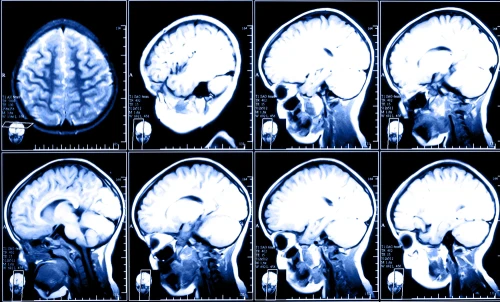

8 brain scans showing various layers and angles, displayed in two rows of 4.

In order to function correctly, the human brain requires a constant oxygen flow. Without oxygen, there is a potential for serious and long-term brain injury. There are two types of brain injuries that involve the loss of oxygen to the brain: anoxic and hypoxic. Both of these types of brain injuries vary in severity based on how long the brain goes without oxygen. Both types of injuries can arise from the same causes, but there are some differences between the two types.